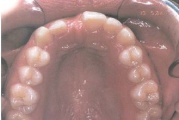

Hambakaaries

Ravijärgne seis. Jäävhammas on täielikult lõikunud.